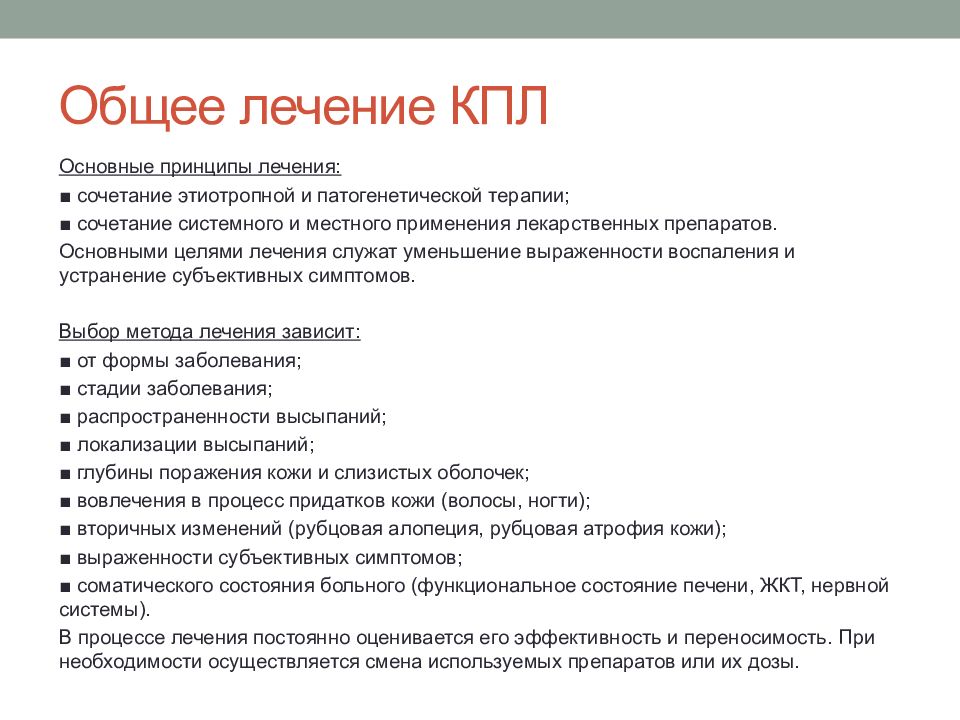

Фото Красного Плоского

Фото Красного Плоского 103 фото